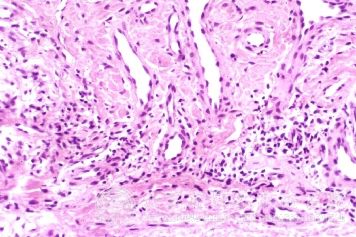

皮肤微*对急性发作湿疹有致病作用:Fujisanva等用交链孢霉、杂色曲霉、枸橼青霉等气源性真菌的浸出液抗原,在夏季复发或加重的急性发作湿疹皮炎患者进行斑贴试验、皮内试验及激发试验。结果皮内试验速发反应阳性率在急性发作湿疹样皮炎、特应性皮炎患者均高于正常对照组,且以特应性皮炎患者较高,为68.2 ,而皮内试验迟发型反应(72小时观察)阳性率在急性发作湿疹样皮炎及特应性皮炎患者均高于正常对照组,以急性发作湿疹样皮炎较高为40 。